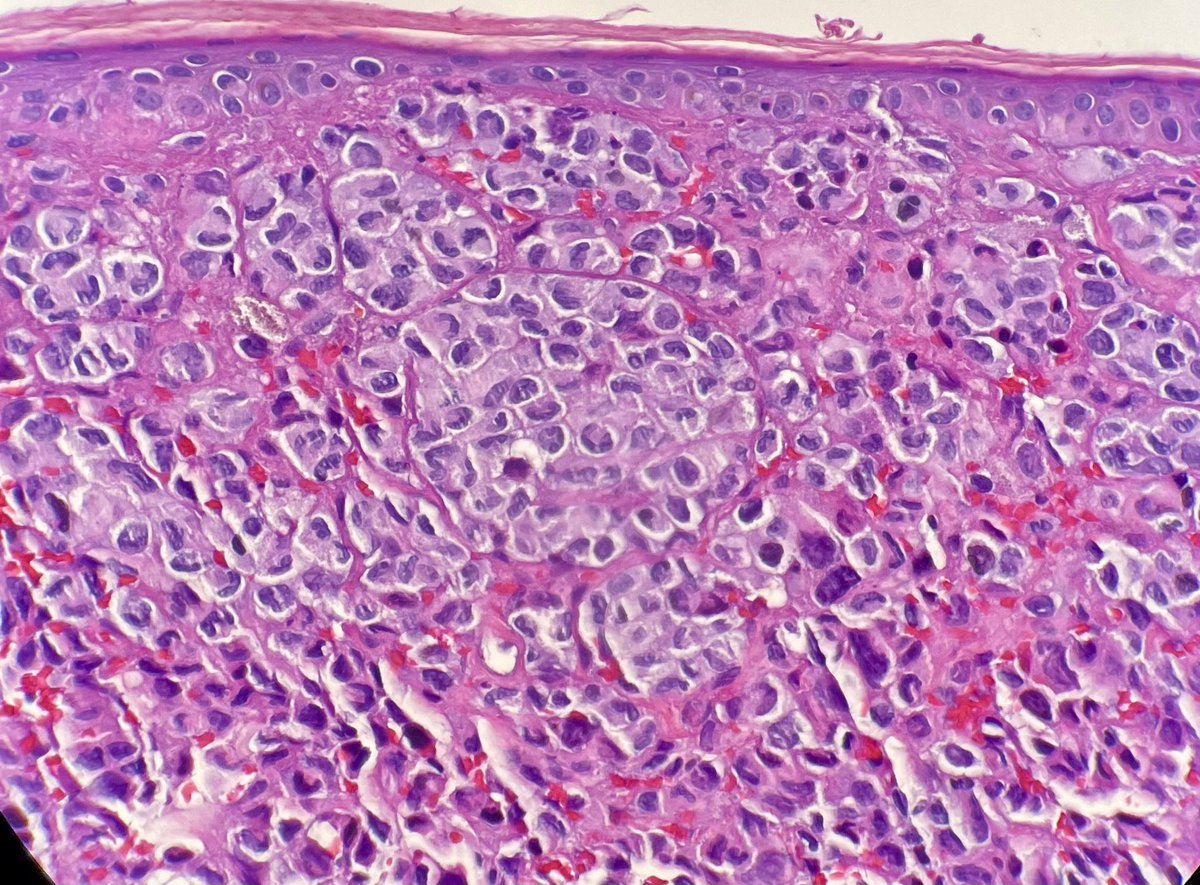

Silvija Gottesman MD Alejandro Gru (Ale) J Cutan Pathol Katy Veprauskas Maxwell Fung, MD Gregory A Hosler Henry YANG David Terrano Dermpath-L Dermpath_doc_trish Tristan Rutland MBBS FRCPA IFCAP Etan Marks, DO Maryam Aghighi, MD. DABP. Jerad Gardner, MD Cacey Peters, MD, FCAP, FASDP Pembe Oltulu, MD Walter Klein MD Andrea P Moy, MD Patrick Rush Jisun Cha MD FAAD Sara Shalin James A. Ramirez Joseph Susa, DO Rosalynn Nazarian MD 🅰🅼🆈🅷🅳🅴🅴🅺🅴🅽🅼🅳 Mariantonieta Tirado Vijay Shankar S Mike DeWall, D.O. Olaleke Folaranmi David Larson Luis Humberto Cruz C Kamran Mirza MD PhD - کامران مرزا Toño Navarro, M.D. 🔬🎗️ Nicole D. Riddle, MD, MSHI, FCAP (she/her) Haneen Salah Save the Date. Save the Date. Hot off the press. Next #dermpathJC to take place on 01/26/23 at 9pm EST, here on Twitter. Open access link at: jamanetwork.com/journals/jaman… #dermpath